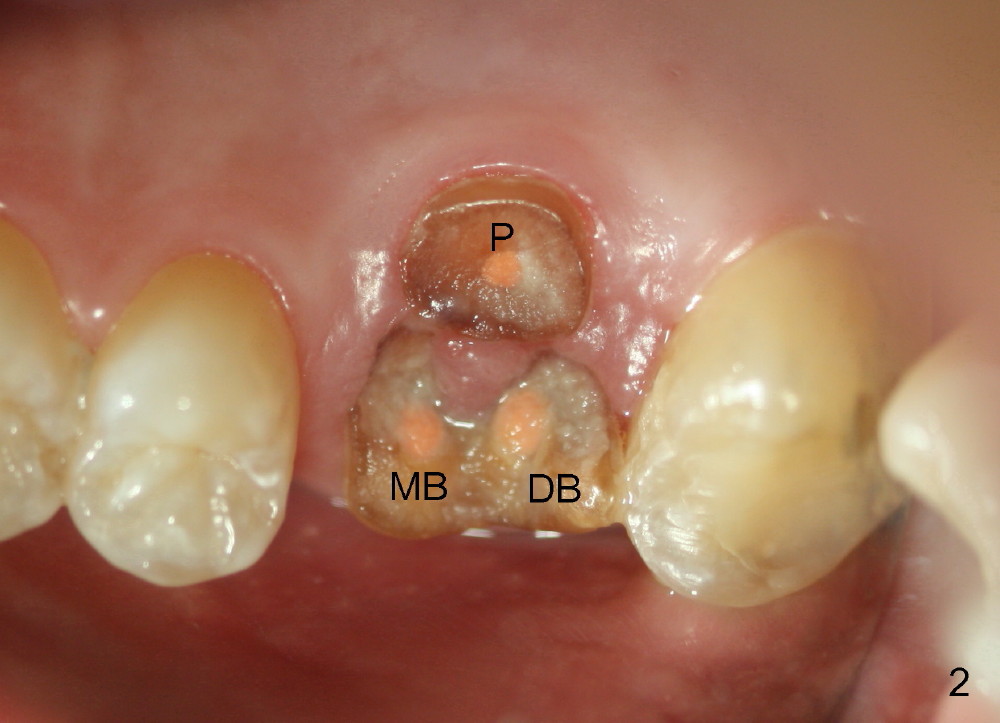

The 1st approach is used for the following case: a 46-year-old man with #14 (Fig.1). The root stumps are large and relatively close to each other (Fig.2 mirror view) so that when the roots are extracted (Fig.3 black), the septum is narrow (white). A 1.2 mm pilot drill penetrates the septum (red).

By the time a 2.6 mm bone expander is used, the septum starts to break off (Fig.4 green). The osteotomy site has to be changed: first to the palatal slope of the palatal socket (red) with the coronal end of the drill leaning buccally. Suddenly a better idea occurs: new osteotomy remains in the palatal socket, but as buccally as possible (blue) and finishes with rounded tapered osteotomes 2-4 mm at ~17 mm deep. The coronal end of the osteotomes is controlled to be positioned in the center of the socket (Fig.5 blue).